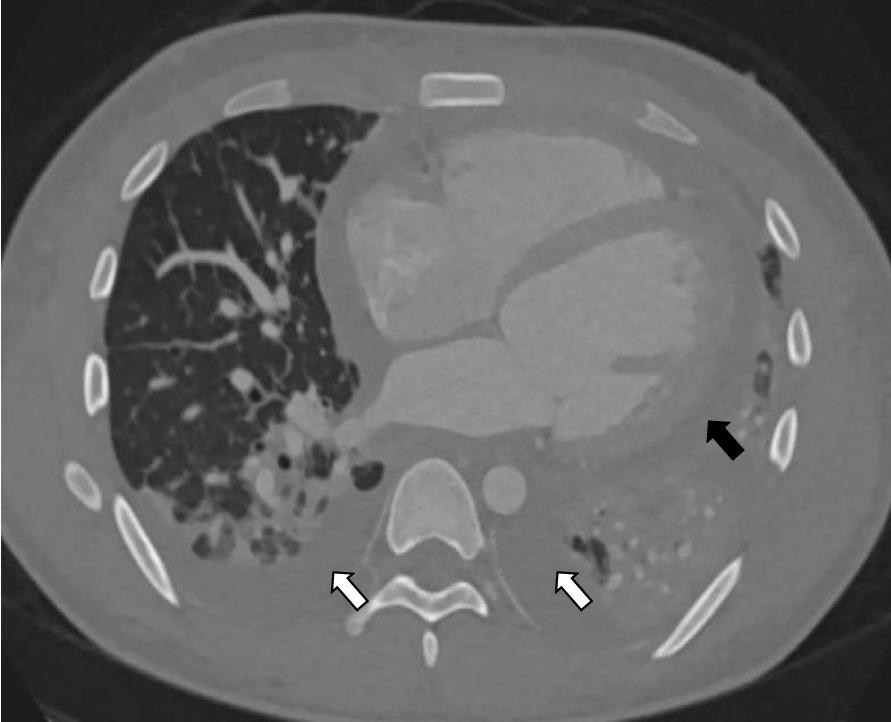

A 20-year-old Filipino male presented with acute dyspnea, pleuritic chest pain, fevers, and diffuse rash after being diagnosed with SLE six months ago and treated with hydroxychloroquine. Labs were notable for leukopenia, non-nephrotic range proteinuria, elevated cardiac biomarkers, inflammatory markers, low complements, and serologies suggestive of active SLE. Broad-spectrum IV antibiotics and corticosteroids were initiated for sepsis and SLE activity. Blood cultures were positive for MSSA with likely skin source. An electrocardiogram showed diffuse ST-segment elevations without ischemic changes. CT chest demonstrated bilateral pleural and pericardial effusions with dense consolidations. Transthoracic and transesophageal echocardiogram demonstrated reduced left ventricular ejection fraction (LVEF) 45% with no valvular pathology suggestive of endocarditis. Although MSSA bacteremia resolved, the patient rapidly developed cardiopulmonary decline with a repeat echocardiogram demonstrating LVEF < 10%. A Cardiac MRI was a nondiagnostic study to elucidate an etiology of decompensation given inability to perform late gadolinium enhancement. Later, cardiac catheterization revealed normal cardiac output with non-obstructive coronary artery disease. As there was no clear etiology explaining his dramatic heart failure, endomyocardial biopsy was obtained demonstrating diffuse myofiber degeneration and inflammation. These pathological findings, in addition to skin biopsy demonstrating lichenoid dermatitis with a granular "full house" pattern was most consistent with SLE myocarditis. Furthermore, aggressive SLE-directed therapy demonstrated near full recovery of his heart failure.

一名 20 岁的菲律宾男性,六个月前被诊断为 SLE 并接受羟氯喹治疗后,出现急性呼吸困难、胸膜炎性胸痛、发热和弥漫性皮疹,实验室检查发现白细胞减少、非肾病范围蛋白尿、心肌标志物升高、炎症标志物升高、补体降低以及提示 SLE 活动的血清学改变。广谱静脉内抗生素和皮质类固醇被用于治疗脓毒症和 SLE 活动。血培养结果为 MSSA,可能来自皮肤。心电图显示弥漫性 ST 段抬高,无缺血改变。胸部 CT 显示双侧胸腔和心包积液伴致密性实变。经胸超声心动图和经食管超声心动图显示左心室射血分数(LVEF)降低至 45%,无提示心内膜炎的瓣膜病变。尽管 MSSA 菌血症得到缓解,但患者迅速出现心肺衰竭,再次超声心动图显示 LVEF<10%。心脏 MRI 无法明确病因,未能进行延迟钆增强,故进行了心脏 MRI。随后的心脏导管检查显示心输出量正常,无阻塞性冠状动脉疾病。由于没有明确的病因可以解释他的严重心力衰竭,因此进行了心内膜心肌活检,结果显示弥漫性肌纤维变性和炎症。这些病理发现,加上皮肤活检显示苔藓样皮炎和“满堂红”模式的颗粒状表现,与 SLE 心肌炎最相符。此外,积极的 SLE 靶向治疗使心力衰竭几乎完全恢复。